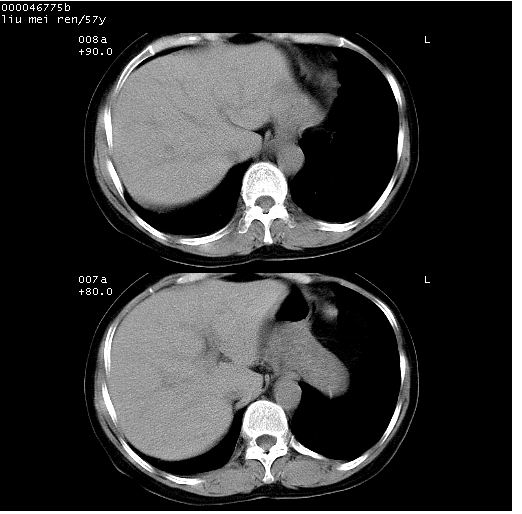

患者 女,57岁。因车祸受伤,其家属要求行“全身ct检查”。平素健康。

胸部ct轴位平扫(层厚10mm,螺距1.5,重建间隔10mm),图像如下: